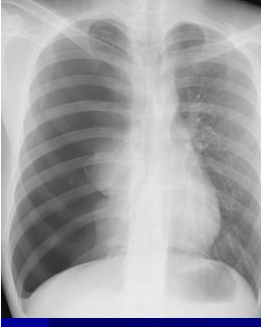

气胸

主诉:胸痛4小时。 现病史:患者4小时前晨起自觉右侧胸痛,针刺样,无放射,不伴喘憋、呼吸困难、发热、咳嗽、咳痰等,就诊我院门诊行胸片检查示右侧气胸,肺压缩约80%。遂为进一步诊治入院。

听诊:左侧呼吸音清,右上肺呼吸音减低。

自发性气胸 胸腔闭式引流